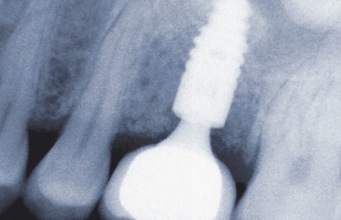

Implantate (von lat. in „im, hinein“ und planta „Steckling, Setzling“) sind kleine künstliche Zahnwurzeln mit etwa 7-11 mm Länge und 3-4 mm Durchmesser. Sie bestehen aus dem körperverträglichen Metall Titan und besitzen eine speziell behandelte Oberfläche, an die sich die Körperzellen besonders gut anlagern und für einen optimalen Halt sorgen. Besonders der Knochen verbindet sich gut mit den Implantaten. Seit über 40 Jahren und über eine Millionen Mal im Jahr in Deutschland werden Titanimplantate benutzt. Bis heute sind noch keine Allergien gegen Titanimplantate bekannt geworden. Titan verhält sich im Körper völlig neutral.